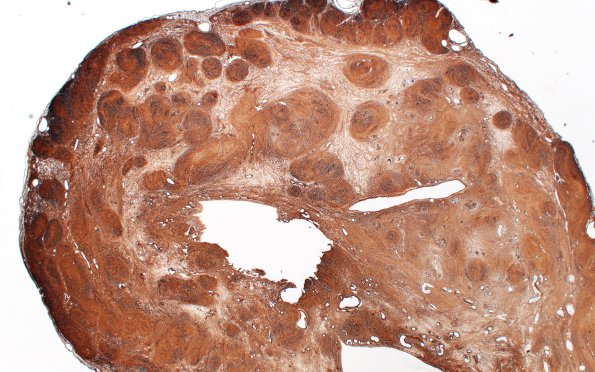

Washington University Experience | NEOPLASMS - CRANIAL AND PARASPINAL NERVEs | Schwannoma | 31D1 Schwannoma, whorled NF2 (Case 31) CollIV 2X

31D1-3 The basement membrane of this tumor is strongly stained for collagen IV. (Coll IV IHC)